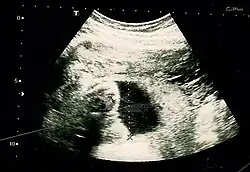

Fetal assessments

Obstetric ultrasonography is routinely used for dating the gestational age of a pregnancy from the size of the fetus, determine the number of fetuses and placentae, evaluate for an ectopic pregnancy and first trimester bleeding, the most accurate dating being in first trimester before the growth of the foetus has been significantly influenced by other factors.[22] Ultrasound is also used for detecting congenital anomalies (or other foetal anomalies) and determining the biophysical profiles (BPP), which are generally easier to detect in the second trimester when the foetal structures are larger and more developed.[23]

X-rays and computerized tomography (CT) are not used, especially in the first trimester, due to the ionizing radiation, which has teratogenic effects on the foetus.[24] No effects of magnetic resonance imaging (MRI) on the foetus have been demonstrated,[25] but this technique is too expensive for routine observation. Instead, obstetric ultrasonography is the imaging method of choice in the first trimester and throughout the pregnancy, because it emits no radiation, is portable, and allows for realtime imaging.[26]

The safety of frequent ultrasound scanning has not been confirmed. Despite this, increasing numbers of women are choosing to have additional scans for no medical purpose, such as gender scans, 3D and 4D scans.[27] A normal gestation would reveal a gestational sac, yolk sac, and fetal pole.[28]

The gestational age can be assessed by evaluating the mean gestational sac diameter (MGD) before week 6, and the crown-rump length after week 6. Multiple gestation is evaluated by the number of placentae and amniotic sacs present.[29]